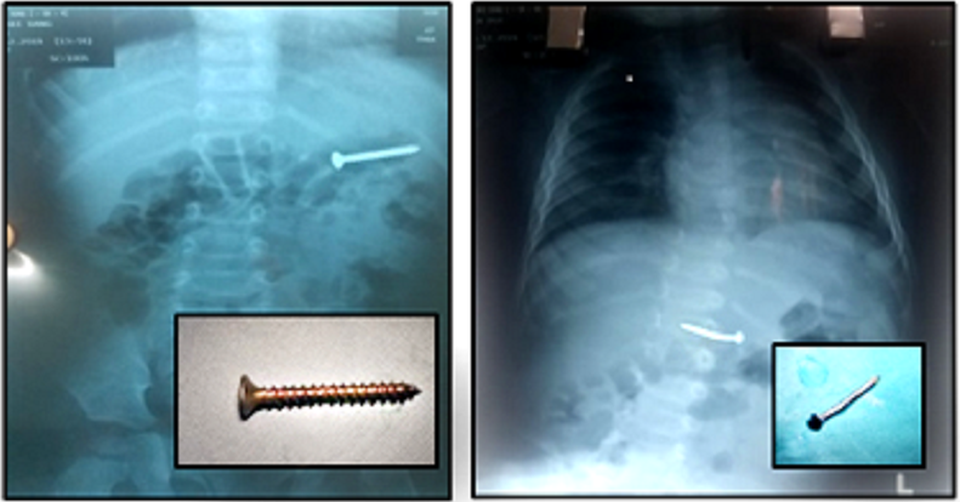

Ngày 20/12, thông tin từ Bệnh viện Nhi Đồng 2, TPHCM cho biết, tại đây vừa liên tục tiếp nhận 2 trường hợp bị dị vật đường tiêu hóa rất nguy hiểm. Trường hợp thứ nhất là bé trai L.M.T. (9 tháng tuổi, ngụ tại Bình Dương) được gia đình đưa đến bệnh viện thăm khám sau khi trẻ có những biểu hiện quấy khóc, bỏ bú. Trên hình ảnh X-quang, bác sĩ phát hiện trong đường tiêu hóa của bệnh nhân có dị vật cản quang hình chiếc đinh có một đầu sắc nhọn.

Dị vật là những chiếc đinh nằm trong đường tiêu hóa của trẻ